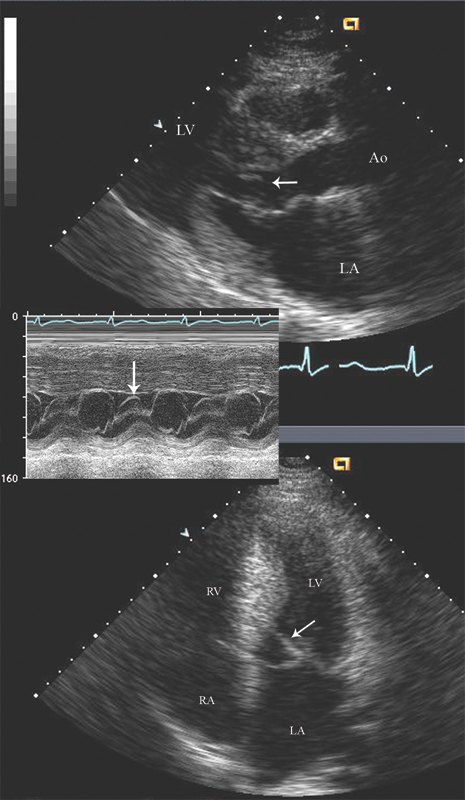

فحوصات تشخيصية لبعض امراض القلب والشرايين التاجية